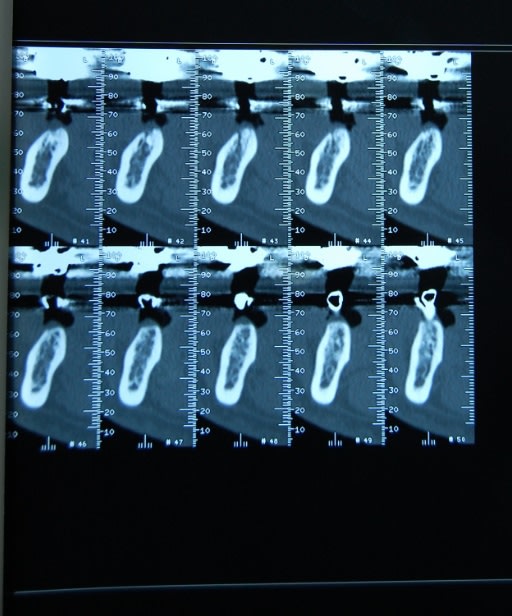

salut ,bien sur deja avec le foret pilote c'etait assez costaud avec des foret neufs(je vais poster le scan)donc dés le debut on allait passer le very hard bone sur toute la longueur ,on a fait ça pour les deux implants avec bonne irrigation .

Salut,l'implant était légèrement supracrestal(une spire) l'edentement avait 15 ans voici le scan.